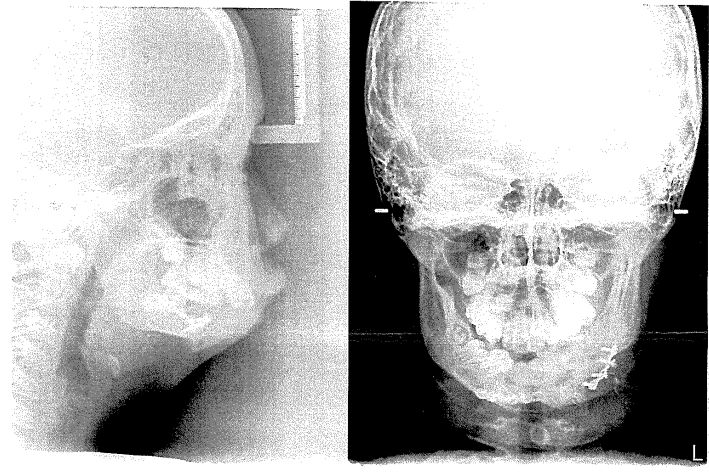

8.一位11歲男性患者在一歲時因為undifferentiatd sacm 切除臼歯區前部的下顎骨,並以迷你骨板及肋軟骨進行即時重建,經過多年的追蹤,目前無復發情况,其目前的頭顱及全口顎X光片如下圖 所示,請問您對於其重建有何想法或策略,採用此种重建策略的依據或原因為何?試說明之。(15%)